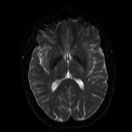

Refer to caption

(a) b = 0 s/mm2

(b) b = 1000 s/mm2

(c) b = 4000 s/mm2

Figure 3: Example axial slice from the STE brain dMRI, involving b-values of 0, 1000 and 4000 s/mm2.

2.6 Brain dMRI by spherical b-tensor encoding

We reused the dataset described in [24]. Images were acquired using the MAGNETOM Prisma 3T (Siemens Healthineers, Germany) system. A research pulse sequence was used [25]. One volunteer was enrolled. However, as the original paper was targeted at dMRI super-resolution reconstruction, eight volumes were acquired with differently rotated fields of view. Namely, the FOV was rotated about the anteroposterior axis, starting in the axial orientation, and then at angles of 22.5, 45, 67.5, 90 (sagittal), 112.5, 135, 157.5 degrees. b-values of 0, 1000 and 4000 s/mm2 were used with 2, 4 and 15 repetitions, respectively, for each field of view. The images have 1.58×\times×1.58×\times×7.2 mm3 voxels and matrix size of 132×\times×132×\times×26. An example slice is shown in Figure 3.